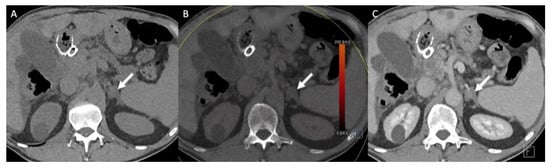

- Hindman, N.M.; Megibow, A.J. One-Stop Shopping: Dual-Energy CT for the Confident Diagnosis of Adrenal Adenomas. Radiology 2020, 296, 333–334. [Google Scholar] [CrossRef]

- Jamali, S.; Michoux, N.; Coche, E.; Dragean, C.A. Virtual unenhanced phase with spectral dual-energy CT: Is it an alternative to conventional true unenhanced phase for abdominal tissues? Diagn. Interv. Imaging 2019, 100, 503–511. [Google Scholar] [CrossRef]

- Nagayama, Y.; Inoue, T.; Oda, S.; Tanoue, S.; Nakaura, T.; Ikeda, O.; Yamashita, Y. Adrenal Adenomas versus Metastases: Diagnostic Performance of Dual-Energy Spectral CT Virtual Noncontrast Imaging and Iodine Maps. Radiology 2020, 296, 324–332. [Google Scholar] [CrossRef]

- Connolly, M.J.; McInnes, M.D.F.; El-Khodary, M.; McGrath, T.A.; Schieda, N. Diagnostic accuracy of virtual non-contrast enhanced dual-energy CT for diagnosis of adrenal adenoma: A systematic review and meta-analysis. Eur. Radiol. 2017, 27, 4324–4335. [Google Scholar] [CrossRef] [PubMed]